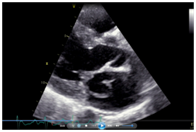

Her echocardiogram showed mild left ventricular and left atrial dilatation with normal left ventricular systolic function. The mitral valve was morphologically abnormal with the anterior mitral leaflet showing an cystic aneurysmal segment with systolic ballooning and some degree of diastolic collapse but incomplete collapse. (Figures 1-3) (Video 1) (Video 2) The aneurysmal segment showed a classical heart shape which was most evident in the end systolic frame. Colour flow imaging showed severe mitral regurgitation with an eccentric jet, the origin of the jet appeared to be through the anterior mitral leaflet. The transeosopheal echocardiography revealed similar findings (Figure 4) (Figure 5)The aortic valve was morphologically normal but for mild cuspal thickening.

Figure 2 The cystic mass in the left atrium in systole.